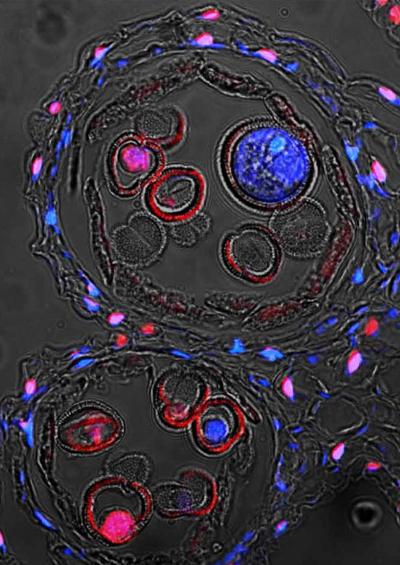

Animal cells are of various sizes and have irregular shapes. A plasma membrane, cytoplasm, ribosomes, and dna. The video compresses 30 hours of mitotic cell. Have a cell membrane, not a cell wall. Animals are eukaryotic living organism that feeds on organic matter, typically having specialized sense organs and nervous system and able to respond rapidly to stimuli. Cell membrane is common to all the cells. Plant and algal cells also have a cell wall, and often have chloroplasts and a permanent vacuole. Animal cells never have cell walls.

The cell (from latin cella, meaning small room) is the basic structural, functional, and biological unit of all known organisms. Plants are not the only organisms whose cells have a wall. Cell structure and function level: A vesicle is another part of plant and animal cells that transports particles and substances to and from the cell. Animals are eukaryotic living organism that feeds on organic matter, typically having specialized sense organs and nervous system and able to respond rapidly to stimuli. Cells are the basic units of all living things including animals, plants, and humans. Plant and animal cells also have. Answer:they all have a nucleus, cytoplasm, cell membrane, mitocondria, explanation The mitochondrion, sometimes called the powerhouse of the cell, is common among complex organisms, which use the. Process that releases energy by breaking down glucose and other food molecules in the presence of oxygen. Chloroplasts work to convert light energy of the sun into. Plants, like animals, must have. The animal cell also has two centrioles which a plant cell doesn't have.

In short, many cells have mitochondria and many don't, and the difference is important. We call this process cell division and cell reproduction, because new cells are formed when old cells divide. Answer:they all have a nucleus, cytoplasm, cell membrane, mitocondria, explanation Both animal and plant cells have mitochondria, but only plant cells have chloroplasts. Animal cells and plant cells have features in common, such as a nucleus, cytoplasm, cell membrane, mitochondria and ribosomes. All cells have at least three common features: Centrioles are used for cell division in animal cells during both mitosis and meiosis by there are many things in common between the two. Animal cells do have vacuoles, but they are smaller, larger in number (plant cells usually have just one or a few large vacuoles) and serve a somewhat different purpose than those of plants. A vesicle is another part of plant and animal cells that transports particles and substances to and from the cell. All eukaryotic cells share common characteristics but also have differences in their cell structures. View all questions by totty. Plant and algal cells also have a cell wall, and often have chloroplasts and a permanent vacuole. Most of the cells size range between 1 and 100 micrometers and are visible only with the microscope.